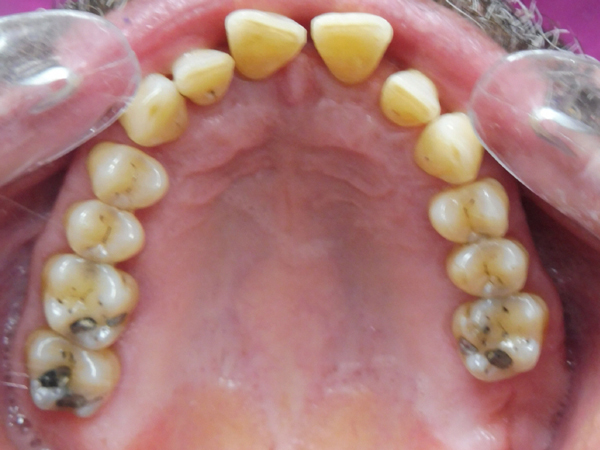

Arcade maxillaire avant traitement orthodontique, séquelles de maladie parodontale

Après traitement orthodontique et réalisation d’une attelle coulée collée (courtoisie Dr Patrick Fournier)